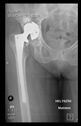

The guiding wire was inserted and controlled with fluoroscopy flashes (Figure 4). The drilling and reaming were carried out in accordance with the recommendations:

Figure 4.

The biocompatible aiming device after insertion of the guiding wire.

In all the cases operated with the above-described targeting procedure, the stems of the cups remained between the cortical bone surfaces without perforation of the linea terminalis, as shown by postoperative radiographs. There were no complicated surgical situations. In 16 cases, the wound healings were uneventful, and the hips were able to bear weight again after postoperative rehabilitation.